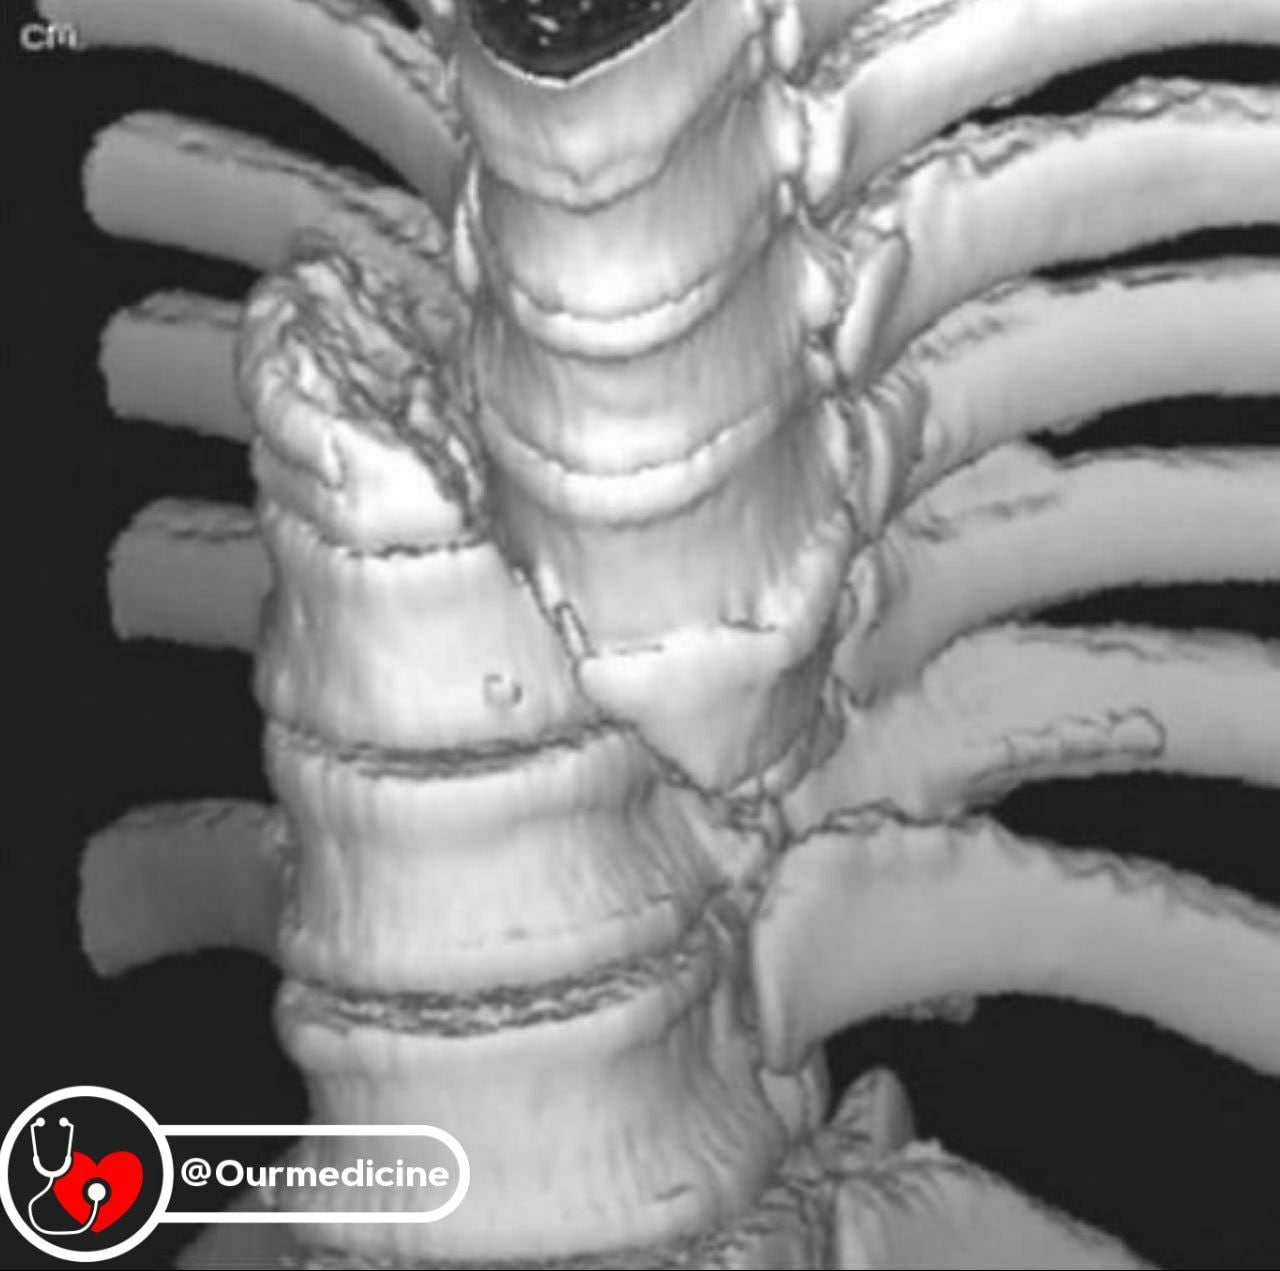

Стабильный перелом позвонка